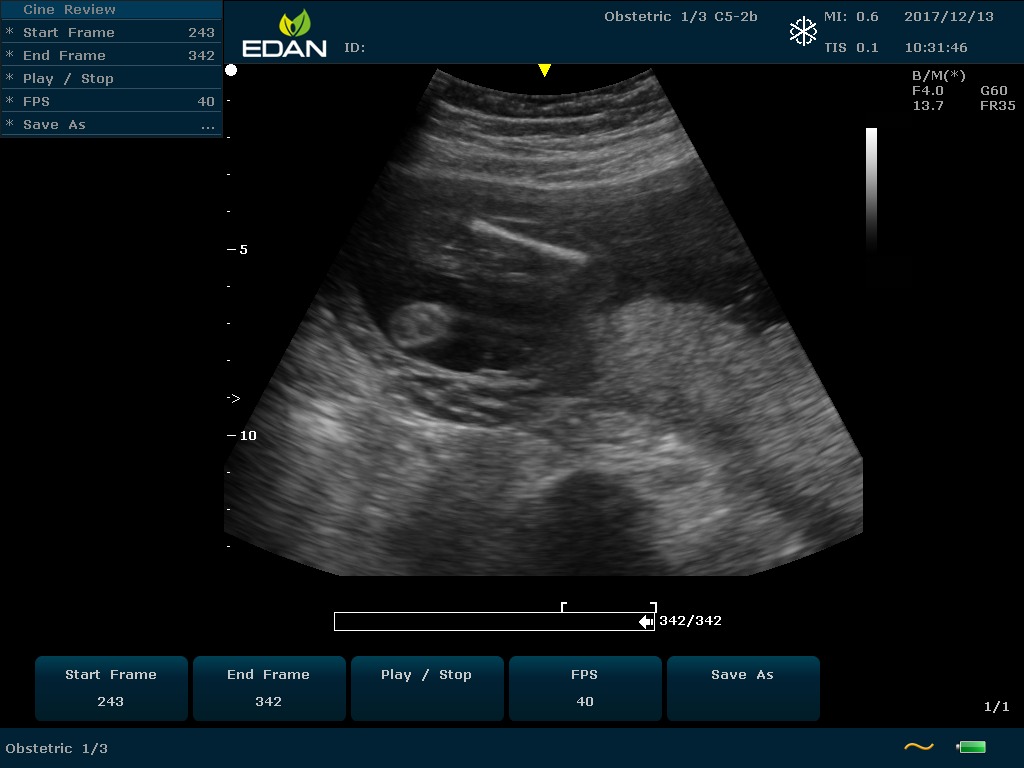

Особенность U60 Edan — расширенное применение. Ультразвуковой аппарат рекомендован для абдоминальных исследований, гинекологии и акушерства, кардиологии, педиатрии, урологии, изучения малых органов, сосудов. Для U60 Edan используются конвексные, линейные, фазированные и внутриполостные датчики.

Передовые технологии позволяют повысить качество визуализации в несколько раз. УЗИ-аппарат U60 Edan отличается возможностью быстрой настройки визуализации. Специальные функции позволяют моментально отображать данные за счет быстрой оптимизации параметров. Режимы визуализации: B-mode, M-mode, Color Doppler, Power Doppler Imaging, Pulsed Wave Doppler, Continuous Doppler.